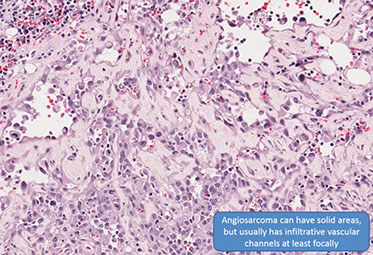

Angiosarcoma

Bland-appearing angiosarcoma with multilayered endotheliom that infiltrates (splits) through collagen

Angiosarcoma can have more solid, spindly areas

Rare tumor in adults, (<1% of sarcomas), ~7th decade (very rare in kiddos) derived from endothelial cells of blood vessels that can occur in multiple sites depending on type of risk factor exposure

Micro: atypical vascular spaced lined by endothelial cells c atypia and multilayering that involves subQ and has RBCs in intracytoplasmic lumina in more solid areas

- lots of mits and necrosis

IHC: (+) Factor 8 related peptide, CD31, Ki-67, FLI-1, thrombomodulin, CD34, c-kit, VEGFR-3, ERG, INI-1 (is lost in epithelioid sarcoma)

Genes: high level MYC amplifications, esp in secondary tumors (post-radiation and in chronic lymphedema; not usually positive in primary sun damaged skin in elderly)